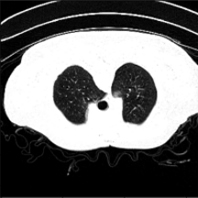

To extract our results, we used two Lung Covid infected datasets, the Covid-19 CT segmentation dataset (noauthor_Covid-19_nodate-1, 23) from which we used only the Segmentation dataset nr. 2, this includes 9 DICOM files of continuous lung CT scans and the 20th April update (jun_Covid-19_2020, 24) which contains another 20 labeled Covid-19 CT scans, from this we used only the 10 files marked as Coronacases and not the Redeopedia ones. The reason for this, is because all DICOM files we used, contained data in the Hounsfield scale (PMID:31613501, 25) the Radeopedia set of DICOM files, contained pixel values in the range of 0-255 therefore we could not use it since it did not follow our normalization procedure. The first set of 9 DICOM files (we refer to this set as CT 1-9), contained 829 slides of CT, having dimensions of 630x630 pixels and includes already hand annotated lung and Covid masks for each slide of it. Similarly, the Coronacases dataset contained 10 CT scans (we refer to this set as CT 10) with 2581 slides in total having dimensions of 512x512 and includes also annotated masks by radiologists of the lung and Covid areas. Both sets, include continuous slides of complete lung CT scans of the same patient and not slides of different patients in each DICOM file. To construct our dataset we used only the slides that include lung areas, in order to achieve better results by reducing the extra information of slides without lung areas. But looking at Table LABEL:table:1, we see that the data in the CT 1-9 dataset use 214 train + 60 validation + 440 test slides total of 714 slides, but we see that the slides with lung areas are in total 713. This happens since one of the slides, marks a tiny area of few pixels as Covid, even if there is no lung or Covid in it, like in Figure 6 (b). This is due to a human error in the annotation procedure. For the normalization process, we resized the images to 320x320 pixels using Nearest Neighbor Interpolation and we kept only the Hounsfield values in the range of -970 to -150. All the information that is needed in our paradigm of Covid segmentation in lung areas, relies in this spectrum of Hounsfield scale. To achieve this, we normalize each pixel based on the following type

Figure 4. 2nd Dataset Good Prediction Example; CT scan (left), Ground Truth (middle), Prediction (right)

We must note here that all the slides that have been used from both datasets, had an area marked as lung in the accompanied mask files from the radiologists. If a slide did not include a lung area, it was not included in the any of the trained/validation or test set data. From the extraction of metrics in the retrained model, we got an average accuracy of 0.9974 and an average F1 score of 0.8279 which was an improvement compared to the 0.6137 F1 before the retrain of the model.